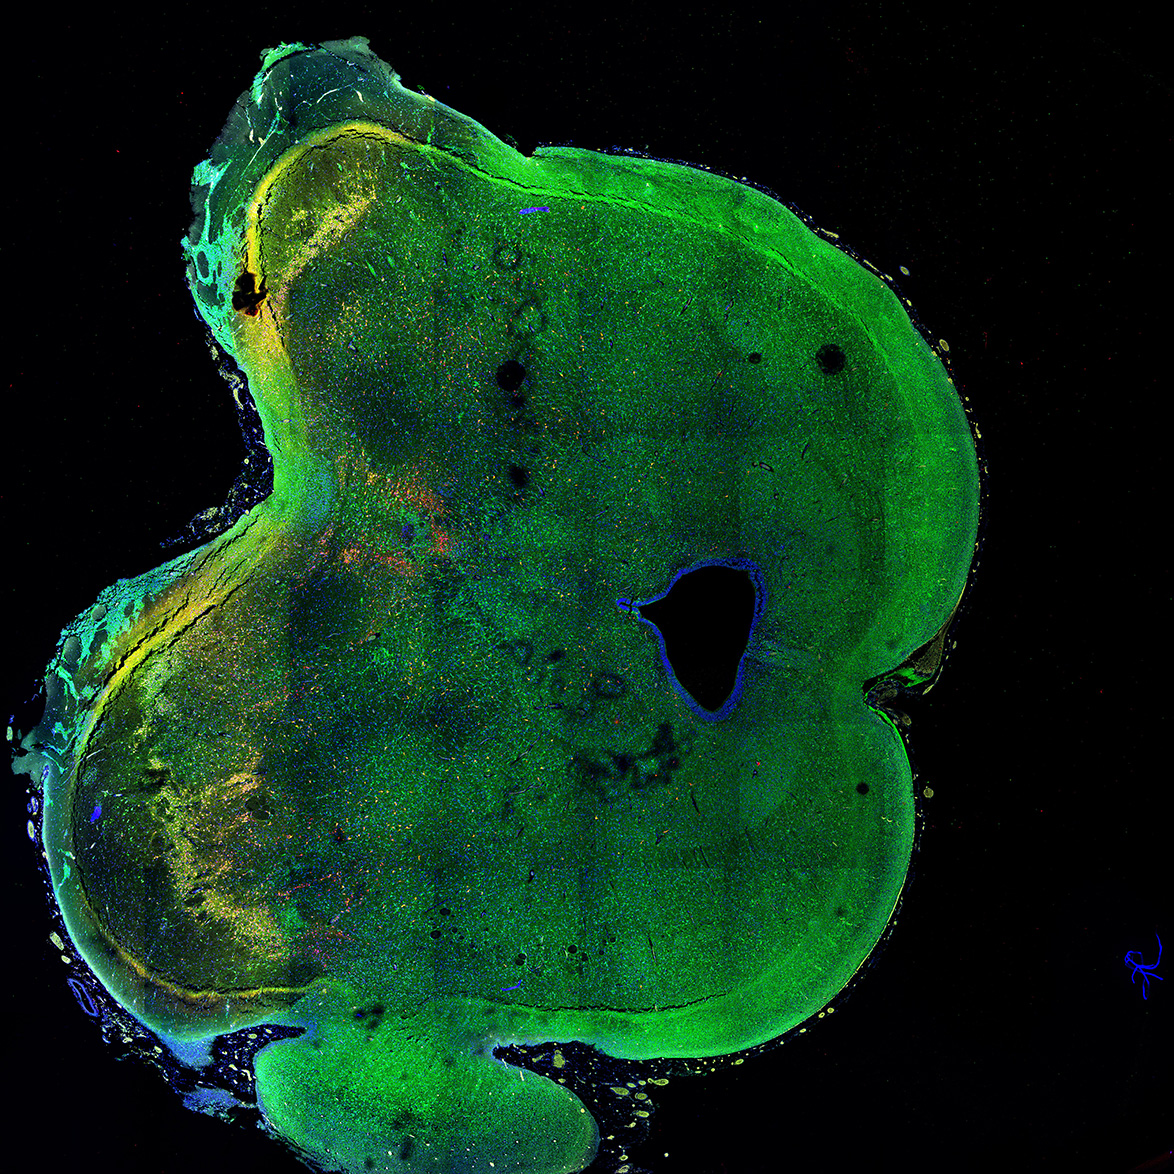

An anatomical analysis of the developing human midbrain from 6 post-conceptional weeks (PCW) to 22 PCW reveals increased tissue complexity, characterized by the emergence of dopaminergic nuclei, as highlighted by immunofluorescence analysis for tyrosine hydroxylase (TH).

11PCW

MAP2

11PCW human midbrain

SOX2

Merged